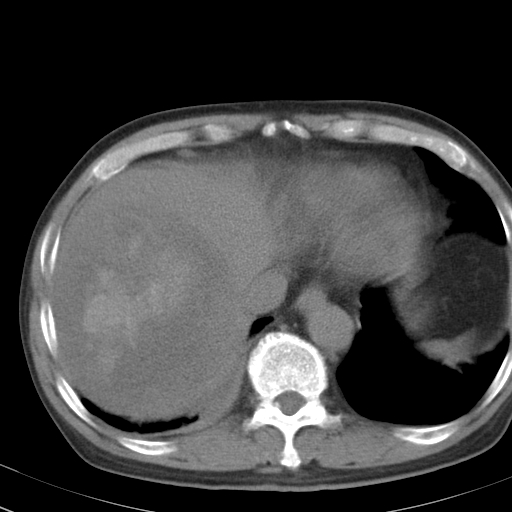

以下是引用卜一在2008-6-23 15:38:00的发言:[br]本例延时期的图象未扫完,单纯平扫 动脉期及门脉期特征分析:平扫低密度较大肿块,内见不规则出血灶,界限清楚。动脉期边缘结节样强化,门脉期病灶边缘进一步强化并范围明显缩小。因此考虑:血管瘤伴出血!

以下是引用深泽交通医院在2008-6-23 16:40:00的发言:[br]考虑肝癌伴出血.诊断依据:平扫瘤壁结节密度低于肝实质,动脉期壁结节明显强化,门脉期略低于肝实质密度[br]病灶有明显的假包膜,